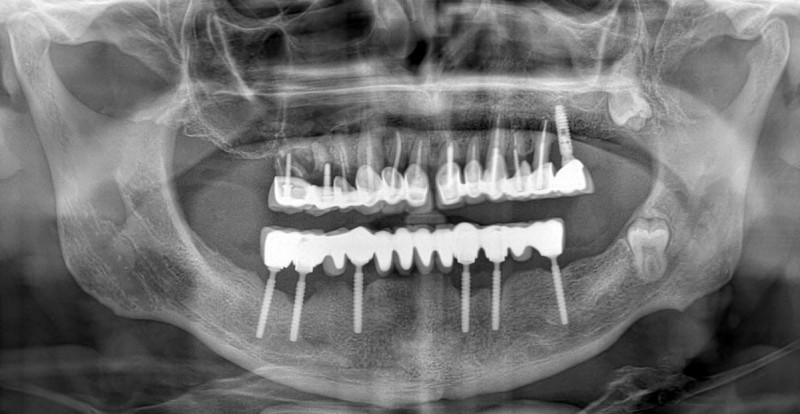

Лечение през 2010 година – мъж на възраст около 30 години с напълно обеззъбена долна челюст. Не желае да носи тотална плакова протеза.

![/userfiles/files/01-cortico-basal-implants.jpg [/userfiles/files/01-cortico-basal-implants.jpg]](/userfiles/files/01-cortico-basal-implants.jpg)

Рентгенова снимка през 2025 година – лека резорбция на костта, нормална за 15 години функционален престой на имплантатите с моста. Пациентът няма оплаквания и се храни нормално.